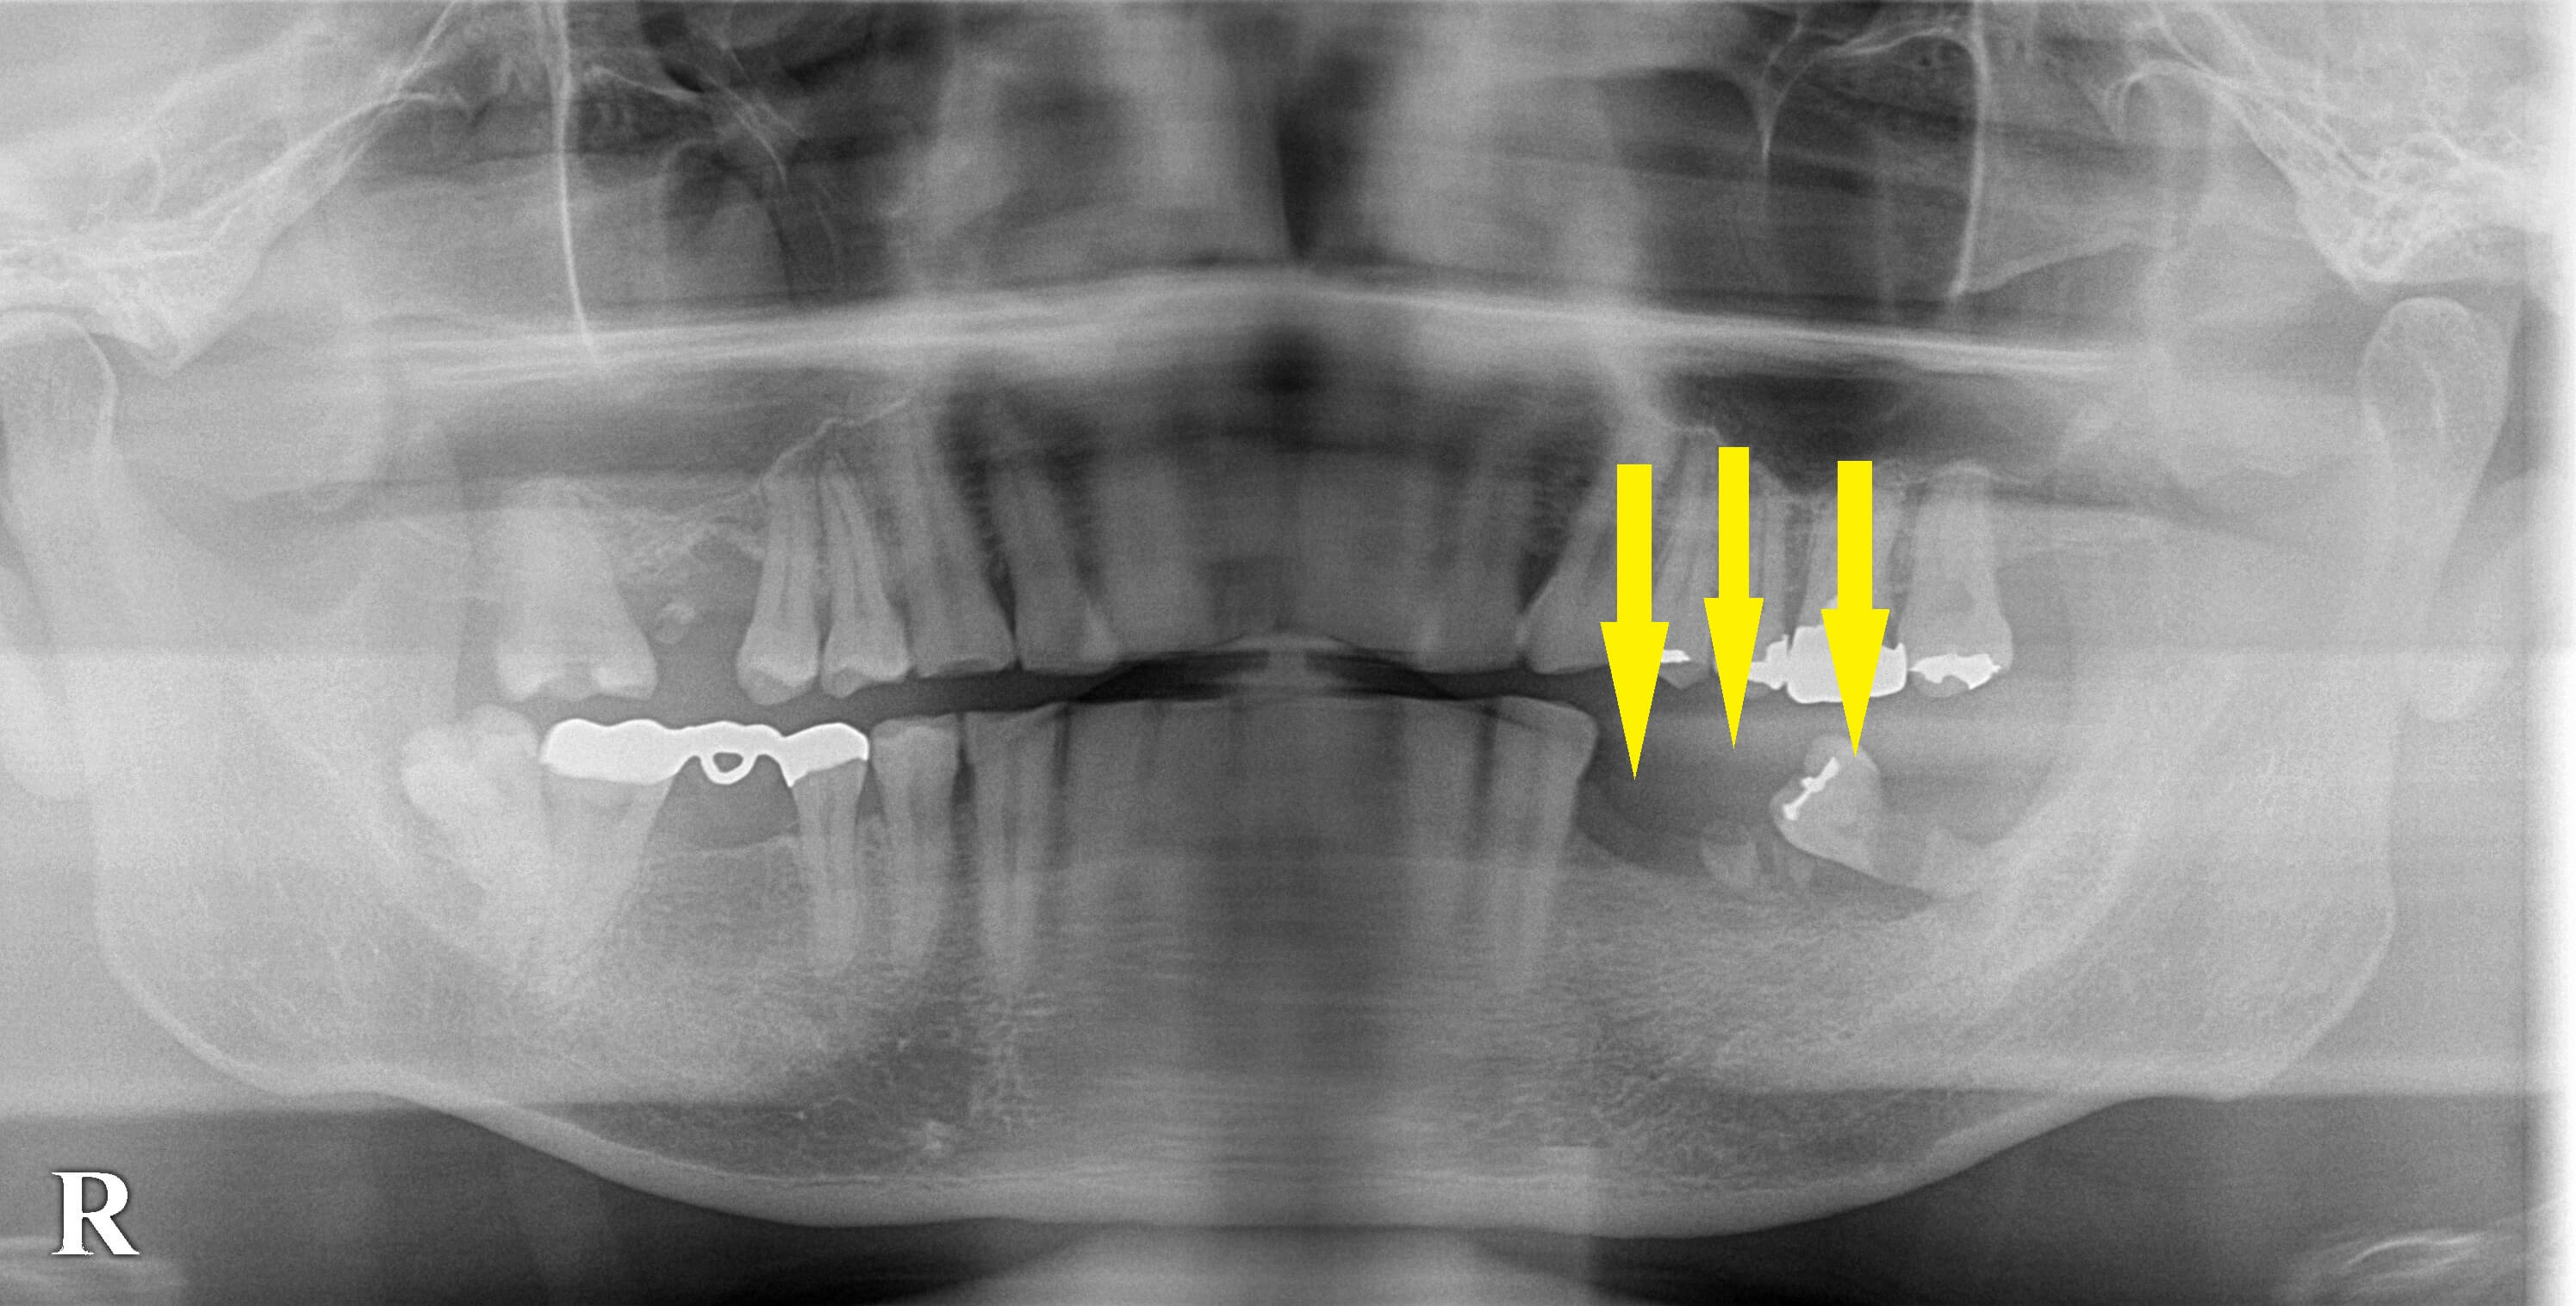

ブリッジできない臼歯欠損は、インプラントで 今週のインプラント症例 2021.08.272026.01.19 患者様は名古屋在住の30代男性。 左下顎の臼歯がボロボロになって久しいとのことですが最近になって親知らずが痛み出し相談においでになりました。 斜めになった親知らずの虫歯が、痛みの原因と思われました。 その前方に、歯根の一部のみが残った歯があり、両方とも保存は不可能でしたので抜歯しました。 インプラント治療を希望されましたので、 この部位に3本のインプラント埋入を行い3歯の回復を行うこととしました。 抜歯後、治癒を待って、本日インプラント埋入術を行っております。 症例・コラム一覧に戻る